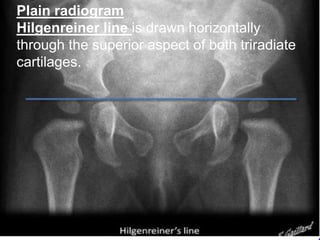

Plain radiogram

Hilgenreiner line is drawn horizontally

through the superior aspect of both triradiate

cartilages.